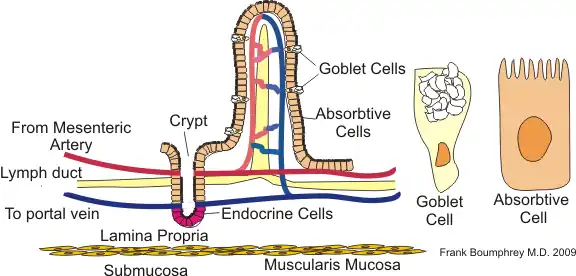

The mucosal layer consists of a epithelial layer, and its underlying supportive tissue, the Lamina Propria. It is separated from the submucosal layer by the Muscularis Mucosa. The epithelial layer varies from section to section of the gut. In the oesophagus it is a non-cornified stratified squamous epithelium; in the stomach it is mainly mucosal cells; the small intestine and large intestine are characterized by absorptive cells, with many mucous producing goblet cells. In the absorptive sections of the intestine, the surface are for absorption is greatly increased by finger-like projections into the lumen called villi, and the absorptive cells themselves also have small projections of microvilli, giving them the appearence of a brush border when viewed with a light microscope.

The lamina propria contains lymph and blood vessels which drain into larger vessels in the submucosal layer. Also in the lamina propria, particularly in the absorptive layers are numerous immune cells, wandering macrophages and lymphocytes, as well as aggregations of lymphoid tissue called called Peyers patches. By some estimates 80% of the body's lymphoid tissue is in the intestine.

The surface for absorption is increased in many ways: the mucosa of the small intestine is thrown into folds called rugae; the mucosa itself has numerous finger-like projections called villi, and the epithelial cells are also covered with numerous projections called microvilli. The microvilli give the appearance of a 'brush' on light microscopy; hence the term brush border. The following illustration shows the anatomy of a villi:

Mucous is secreted by numerous goblet cells; other cells are specialized for absorption and are known as absorptive cells. In the base of the crypts are numerous secretory cells which secrete the digestive enzymes of the small intestine. Some of the crypts penetrate into the submucosal layer, forming digestive glands which will communicate with the mucosa via a secretory duct.